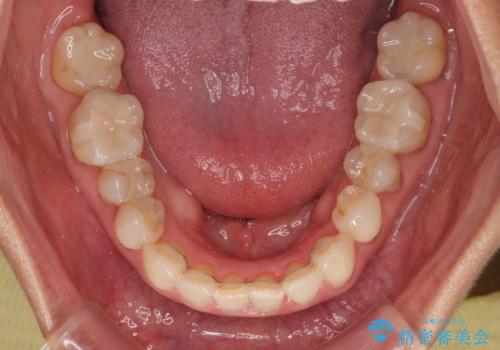

- 前歯のデコボコと口を開けたときに見える銀歯を気にして来院された患者様です。

ある程度デコボコが解消されれば大丈夫とのことで、インビザライン・モデレートパッケージを利用して歯列を整えて行くこととしました。

矯正治療後に銀歯をセラミッククラウンなどに置き換えていくと、どうしても後戻りを起こしてしまうため、矯正治療が概ね終了した時点で銀歯を全てセラミックとし、最後に仕上げでインビザラインにを用いて細かいデコボコを改善していくこととしました。